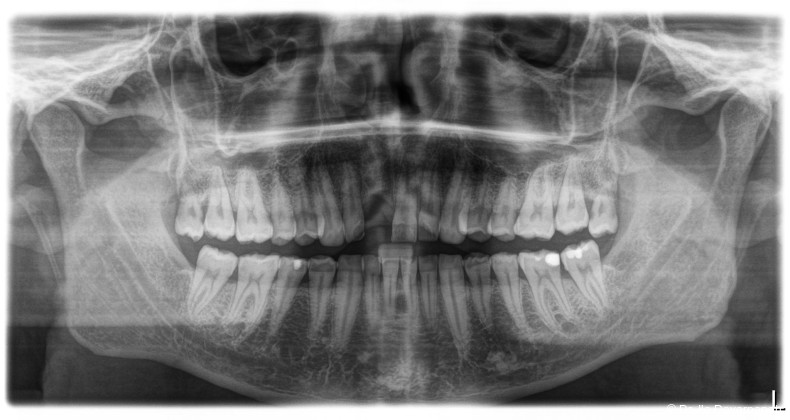

Neben patientenbezogenen und chirurgischen Faktoren spielt dabei auch das Implantatdesign eine wesentliche Rolle. Die vorliegende Falldokumentation zeigt eine Sofortimplantation Regio 11 mit digitaler Planung anhand von DICOM- und STL-Daten. Die präoperative Planung erfolgte softwaregestützt, die Implantatposition wurde prothetisch orientiert festgelegt. Klinisch und radiologisch lagen günstige Ausgangsbedingungen für eine Sofortimplantation mit Sofortversorgung vor.

Postoperativ kam es trotz korrekter Implantatpositionierung und regelrechter Sofortversorgung zu einer Fraktur des Implantatkörpers im Bereich der Implantatschulter. Die radiologische Diagnostik mittels Röntgen und DVT zeigte ein Aufplatzen des Implantats im Übergangsbereich zwischen Konusverbindung und Implantatplattform. Das Frakturmuster deutete auf eine strukturelle Überlastung im hoch beanspruchten Schulterbereich hin. Implantatfrakturen stellen insgesamt eine seltene, jedoch für Patient und Behandler belastende Komplikation dar. Sie treten bevorzugt in Regionen mit erhöhten Biege- und Querkräften auf, insbesondere in der Frontzahnregion und bei frühzeitiger funktioneller Belastung.

Im vorliegenden Fall lag der Fokus der Analyse weniger auf der chirurgischen Umsetzung oder der Indikationsstellung, sondern auf der mechanischen Belastbarkeit. Der Schulterbereich eines Implantats ist biomechanisch besonders exponiert, da hier funktionelle Kräfte konzentriert eingeleitet werden. Unterschiedliche konstruktive Ansätze versuchen, diese Belastung durch Modifikationen der Verbindung oder der Kraftübertragung zu reduzieren. Insbesondere bei Sofortimplantationen mit Sofortversorgung ergeben sich erhöhte Anforderungen an die mechanische Reserve des Systems.